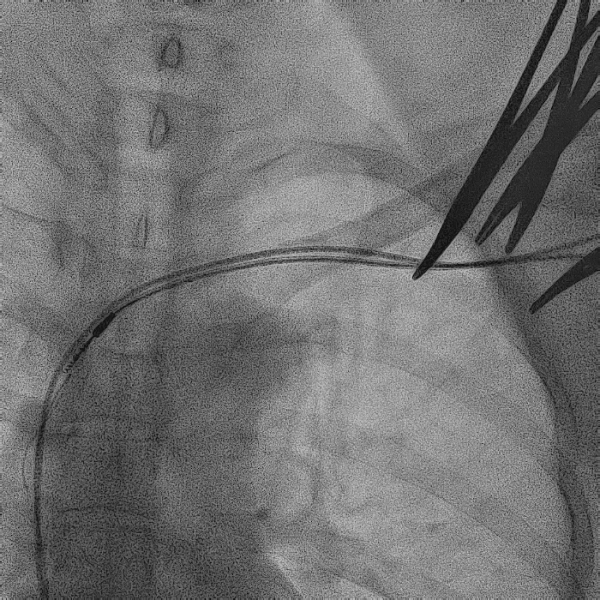

电极拔除

打开囊袋取出原起搏器后,使用锁定钢丝锁定分别锁定两根导线,备用激光鞘并未使用。直接徒手顺利拔除两根导线。

电极拔除过程